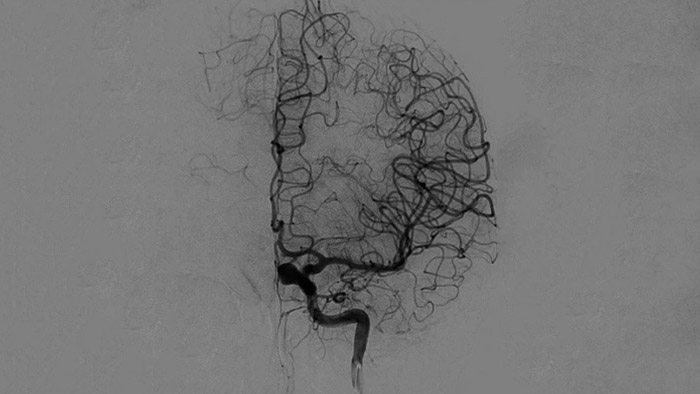

Visualización de la ASD

Las visualizaciones de la ASD de alta calidad le permiten evaluar si ha recuperado el coágulo completo y si los trozos de coágulo se han dispersado distalmente en el cerebro. Puede comprobar el restablecimiento del flujo sanguíneo en la penumbra y comprobar si hay hemorragias periprocedimiento.